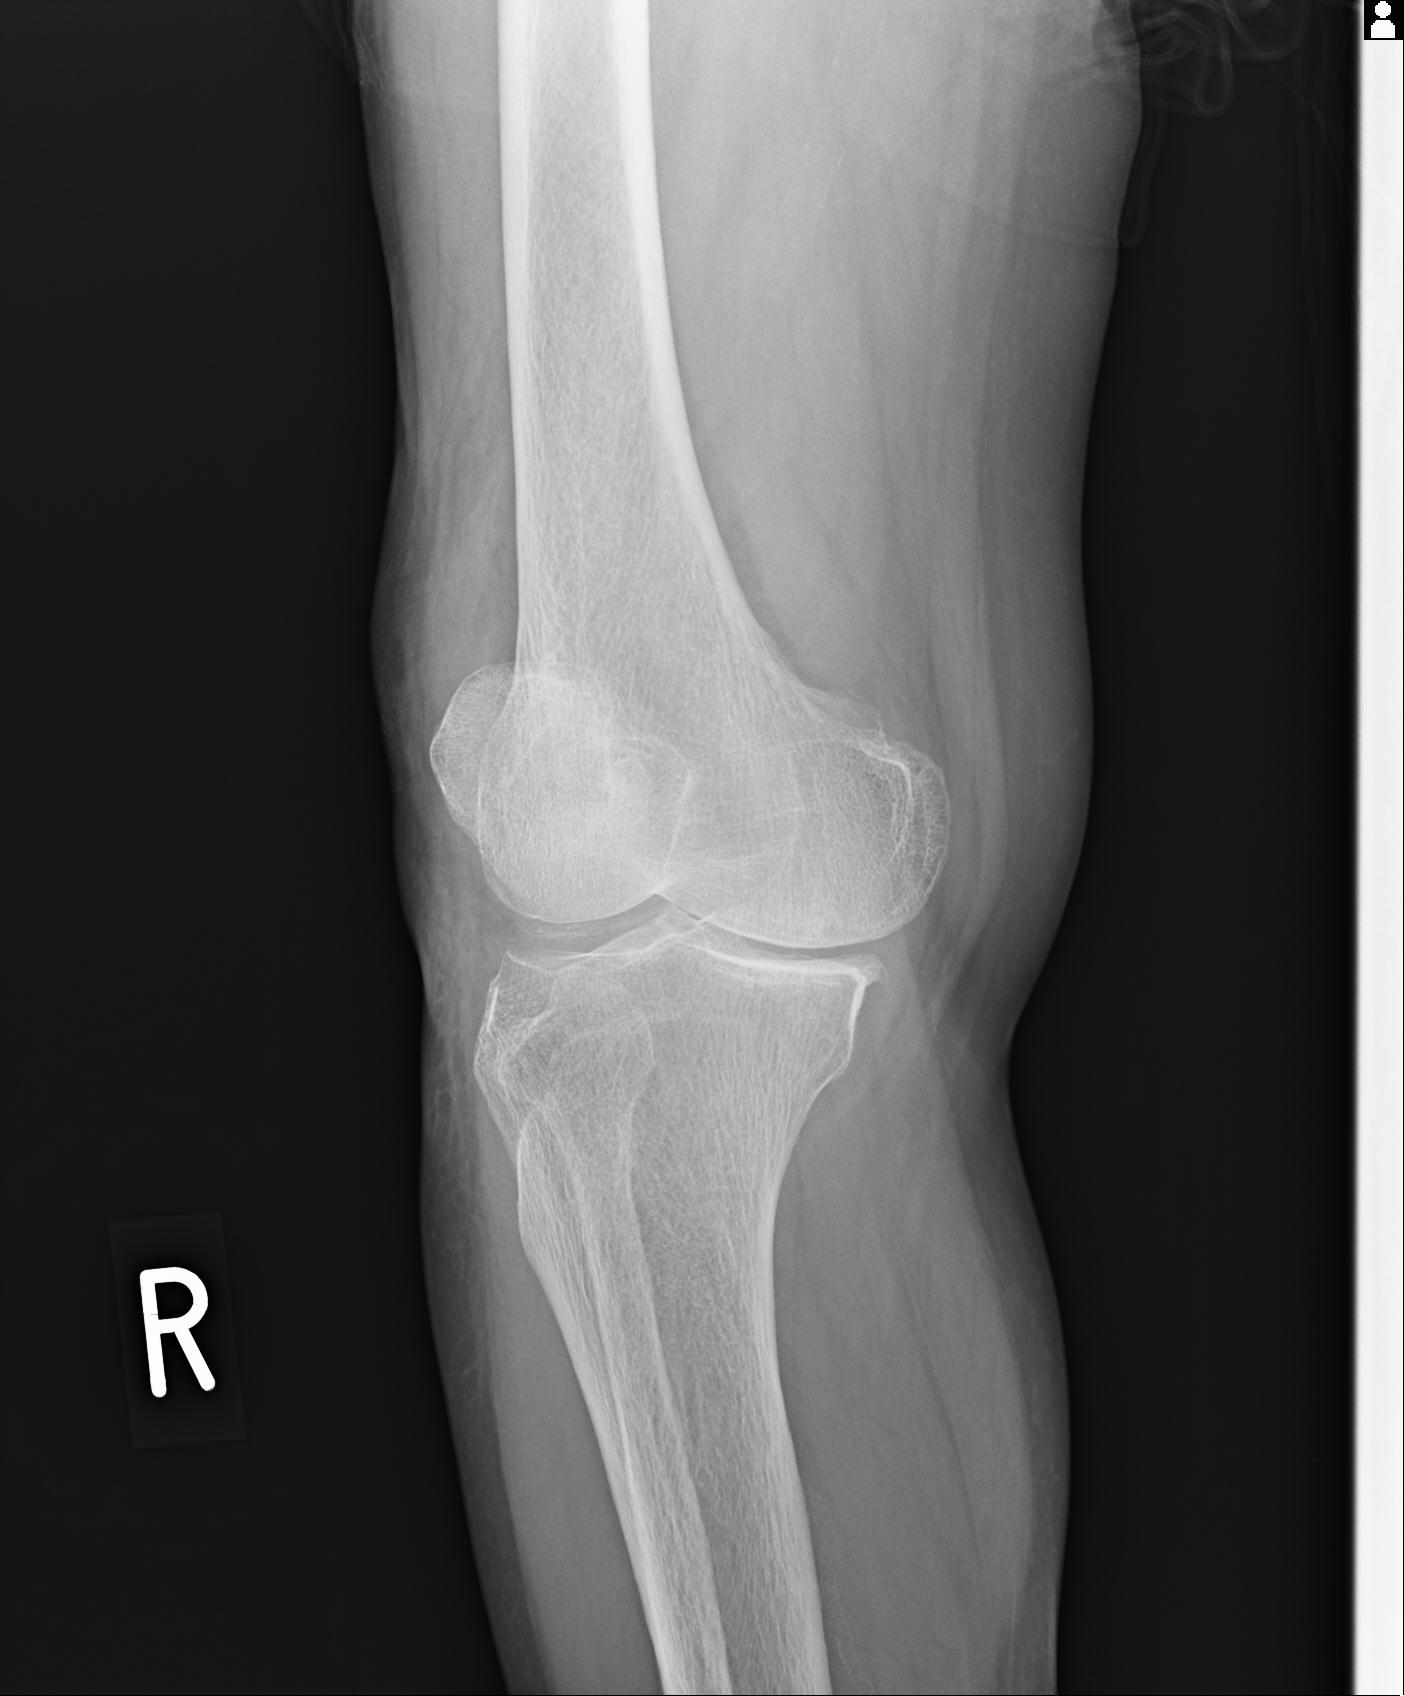

91983 11/16 左膝 2R 11/18 2R 55歳男性 脛骨骨切り術